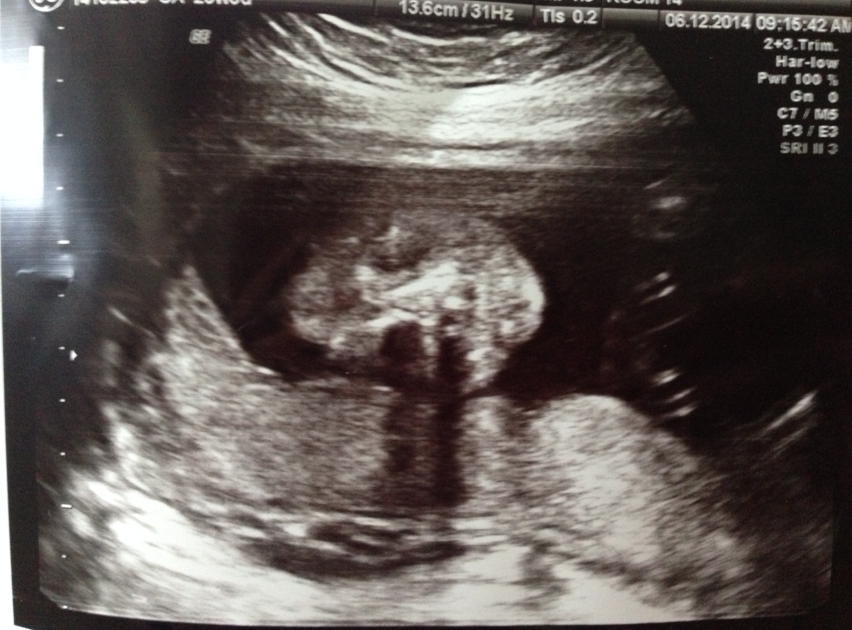

BB呱塊面丫﹗見唔見到骷髏頭咁嘅頭骨?兩個黑色嘅圈圈就係眼框囉~唔知BB呱眼睛係咪都好似爸爸媽媽咁大呢?係咪都係眉粗粗?似爸爸個鼻高啲定係似媽媽個鼻扁啲?

鼻哥窿s同埋嘴嘴﹗你有冇媽媽熱情嘅厚嘴唇呢?

好,我哋睇下臍帶以下,兩脾之間⋯

我都convinced嘅,今次呢個檢查睇落應該係女仔嚟嘅~咁當然影像嘅嘢冇話100%準確㗎啦~umum⋯下次再檢查時confirm一下啦,heehee~之前一直諗住20週照到就可以買嘢啦,點知照完之後好似又等23週時再睇睇再買啦⋯心大心細添~